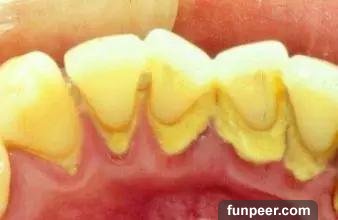

什麼是牙結石牙結石又稱牙石,通常存在於唾液腺開口處的牙齒表面。如下顎前牙的舌側表面,上顎後牙的頰側表面和牙齒的頸部,以及口腔黏膜運動不到的牙齒表面等處。牙結石最開始是乳白色的軟垢,通過逐漸鈣化變硬。它是由75%的磷酸鈣,15%~25%的水、有機物、磷酸錳、礦酸鈣及微量的鉀、鈉、鐵所構成。牙結石通常呈現出黃色、棕色、或黑色等,有的與自然牙顏色相近,有的則明顯可見差異。

牙結石從牙冠逐漸向下蔓延,牙結石每進步一些,牙槽骨就萎縮一些,久而久之,牙齒就逐漸松動,牙結石便見縫插針,逐漸蔓延到牙根部位。對口腔而言,結石是一種異物,它的存在本身就會不斷刺激牙周組織並壓迫牙齦,影響口腔局部血液循環,造成牙周組織病菌感染,引起牙齦發炎萎縮,形成牙周袋。當牙周袋形成後,食物殘渣、牙菌斑和結石等更易堆積,進一步的破壞更深的牙周膜,如此不斷的惡性循環的結果,終至牙周支持組織全部破壞殆盡,牙齦出血、牙周疾病等隨之而來。總而言之,如不能及時清除,被牙結石纏上的牙齒最終逃脫不了潰爛脫落的命運。作為口腔健康的一級殺手,牙結石的存在不容忽視。值得注意的是,在牙結石形成之初由於硬度較小,使用口腔清潔或刷牙等方法往往較容易清除,而隨著日積月累的鈣化、牙結石在口腔中緊密附著,普通的刷牙或口腔清潔方法便難以將其去除了。相信有的朋友在閱讀文章的時候就已經按耐不住“攬鏡自照”來確認自己口中有沒有被牙結石入侵了吧?不用過分擔心,接下來將傳授給大家對抗之法,幫助大家戰勝這位牙周疾病的罪魁禍首、口腔中的大惡魔。牙結石的清除方法經過鈣化的牙結石難以通過刷牙等傳統方式清潔,但口腔潔治可以做到,也就是通常說的洗牙。洗牙有手工掛治和超聲潔治兩種,目前大部分醫院和診所采用的是超聲潔牙。手工刮治通過比較精細的齦下刮治器刮除牙齒附著的牙石和菌斑。而超聲潔牙機則通過高頻率震蕩傳導至特制工作尖,將能量集中在工作尖並釋放,對頑固堅硬的牙結石產生較大的衝擊力,並將其震碎,使其從附著的牙面脫落。同時,超聲震蕩產生的水霧將環繞在工作尖的周圍,將牙結石的碎屑衝洗殆盡。

兩種方法都可以去除牙結石,但相比傳統手工潔牙,超聲潔牙更加高效、同時更加舒適無痛。特別是針對肉眼不可見的齦下牙結石、牙菌斑等的去除,超聲潔牙效率更勝一籌。